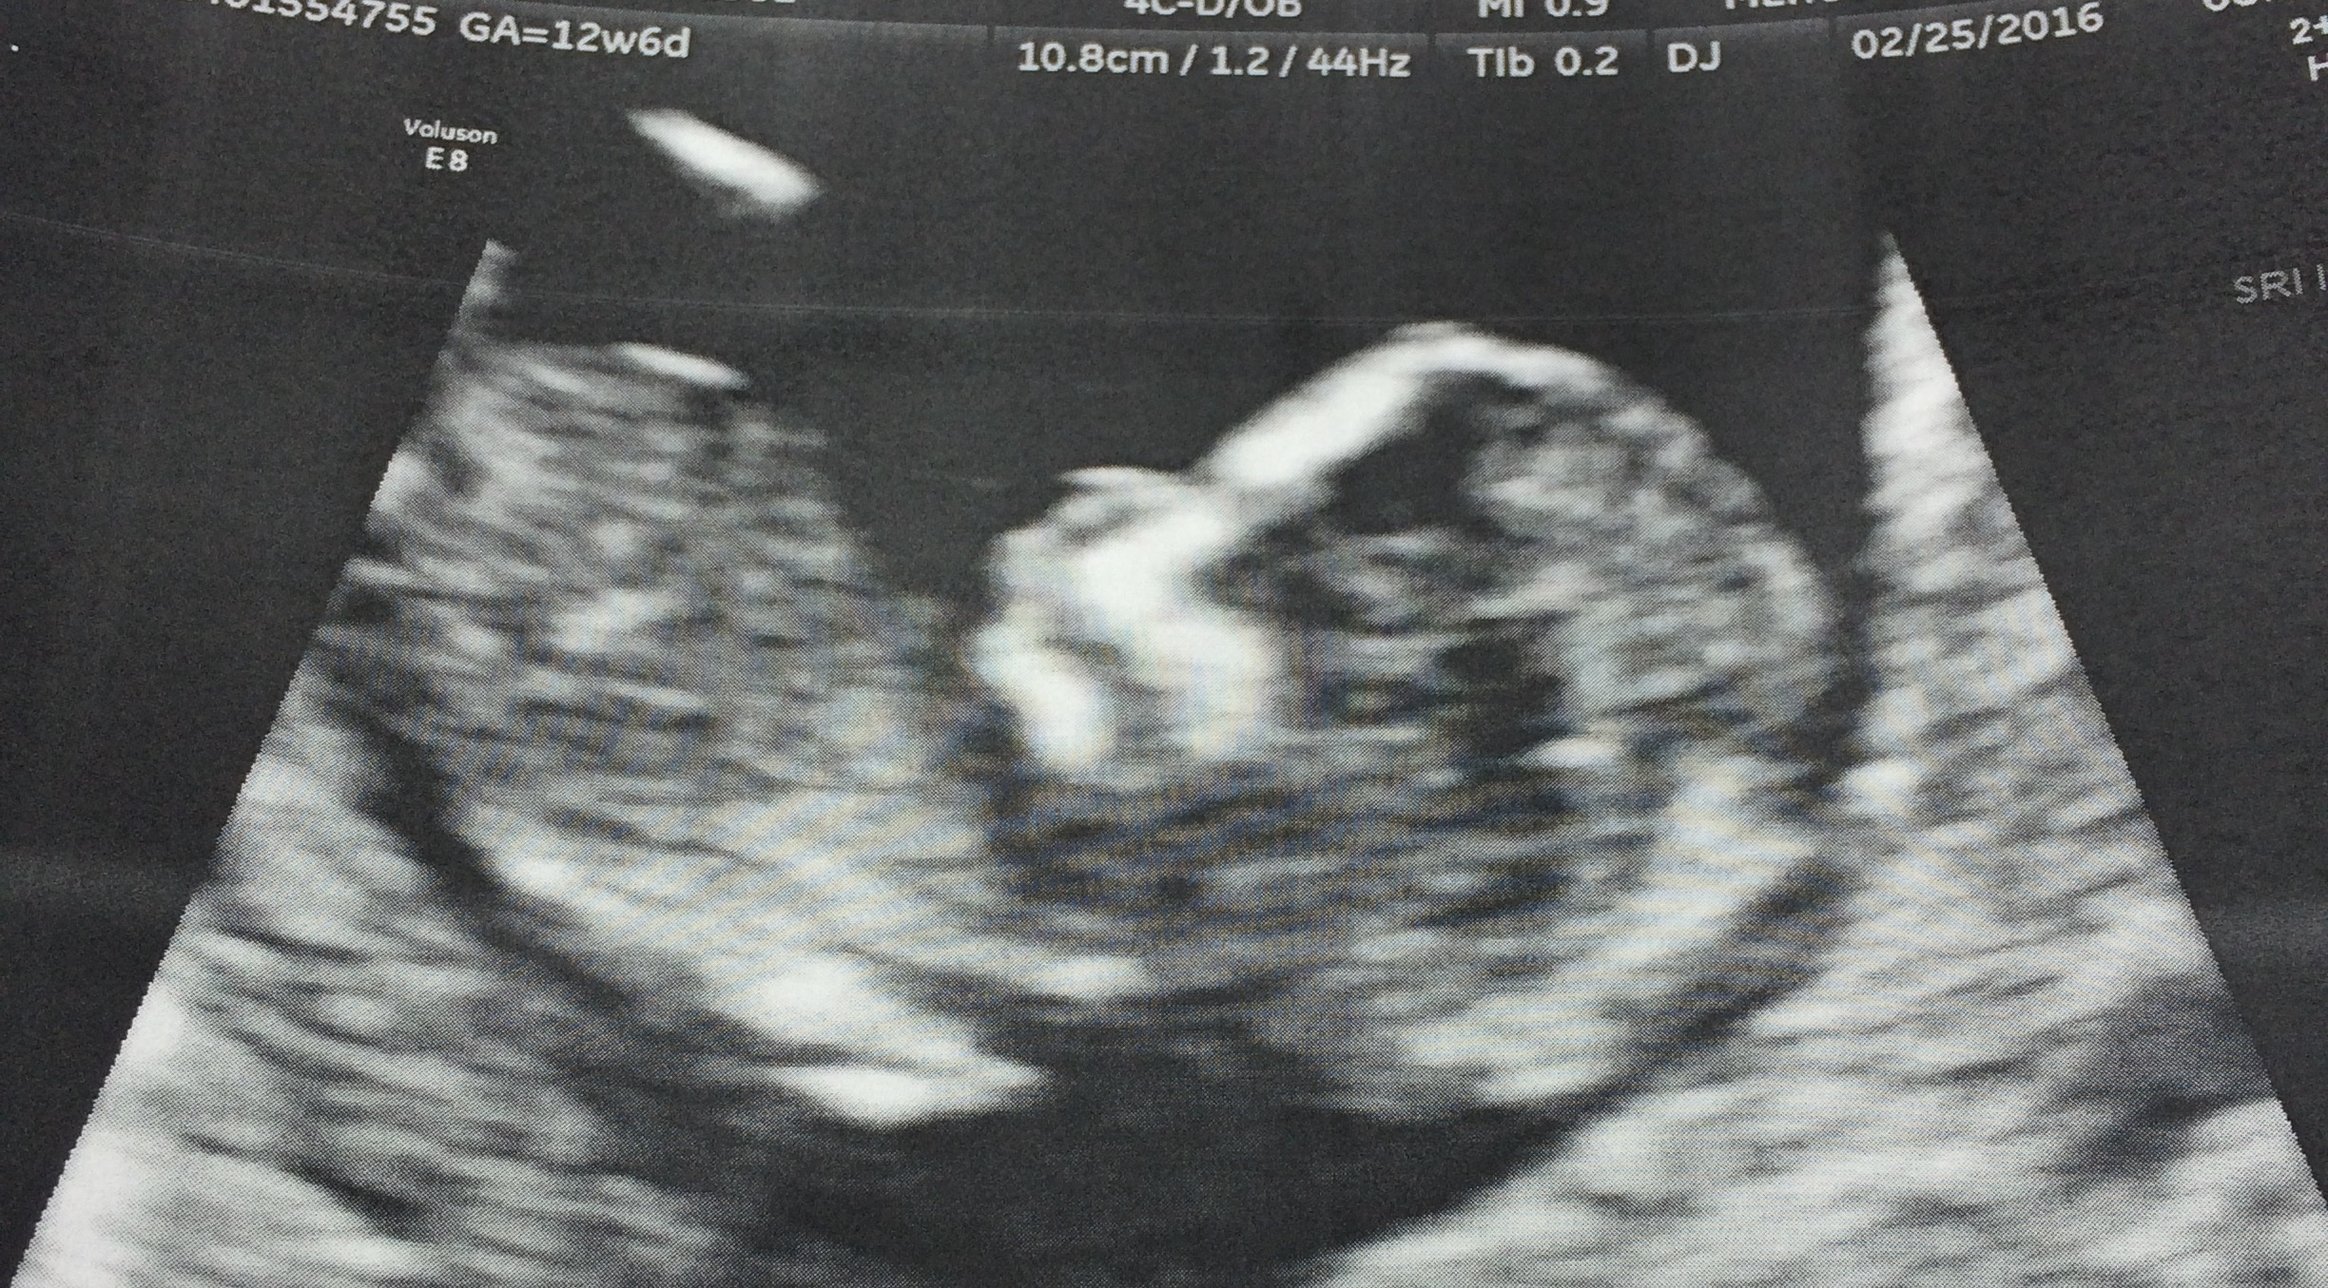

Finally! Met our rainbow baby yesterday, measuring spot on at 10w+1 and heartbeat at about 150/min. LO had the sweetest hiccups that we could see on the u/s, I'm in love!